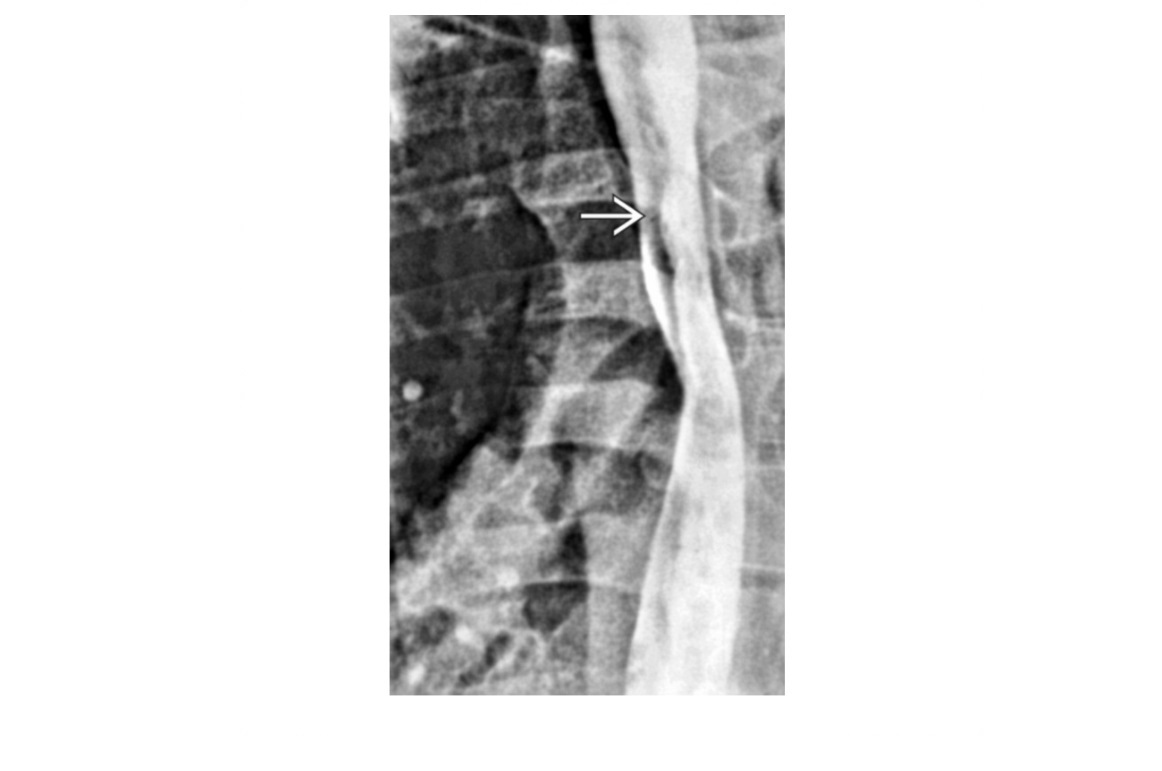

HHT **Tortuous and prominent hepatic arterial branches ** Dilated hepatic veins and early filling Arterial phase, mosaic attenuation of the liver with multiple enhancing foci aka Osler-Weber-Rendu syndrome Hereditary multiorgan disorder → fibrovascular dysplasia with development of telangiectasias and arteriovenous malformations (AVMs)